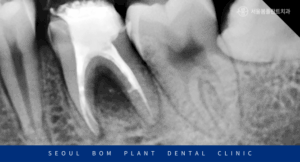

촬영 날짜 : 2025.03.25

2년이 경과한 뒤의

x-ray 사진인데요.

처음 내원 당시와

비교해 보면 골재생이 많이 되어

안정적인 예후를 확인할 수 있었습니다.